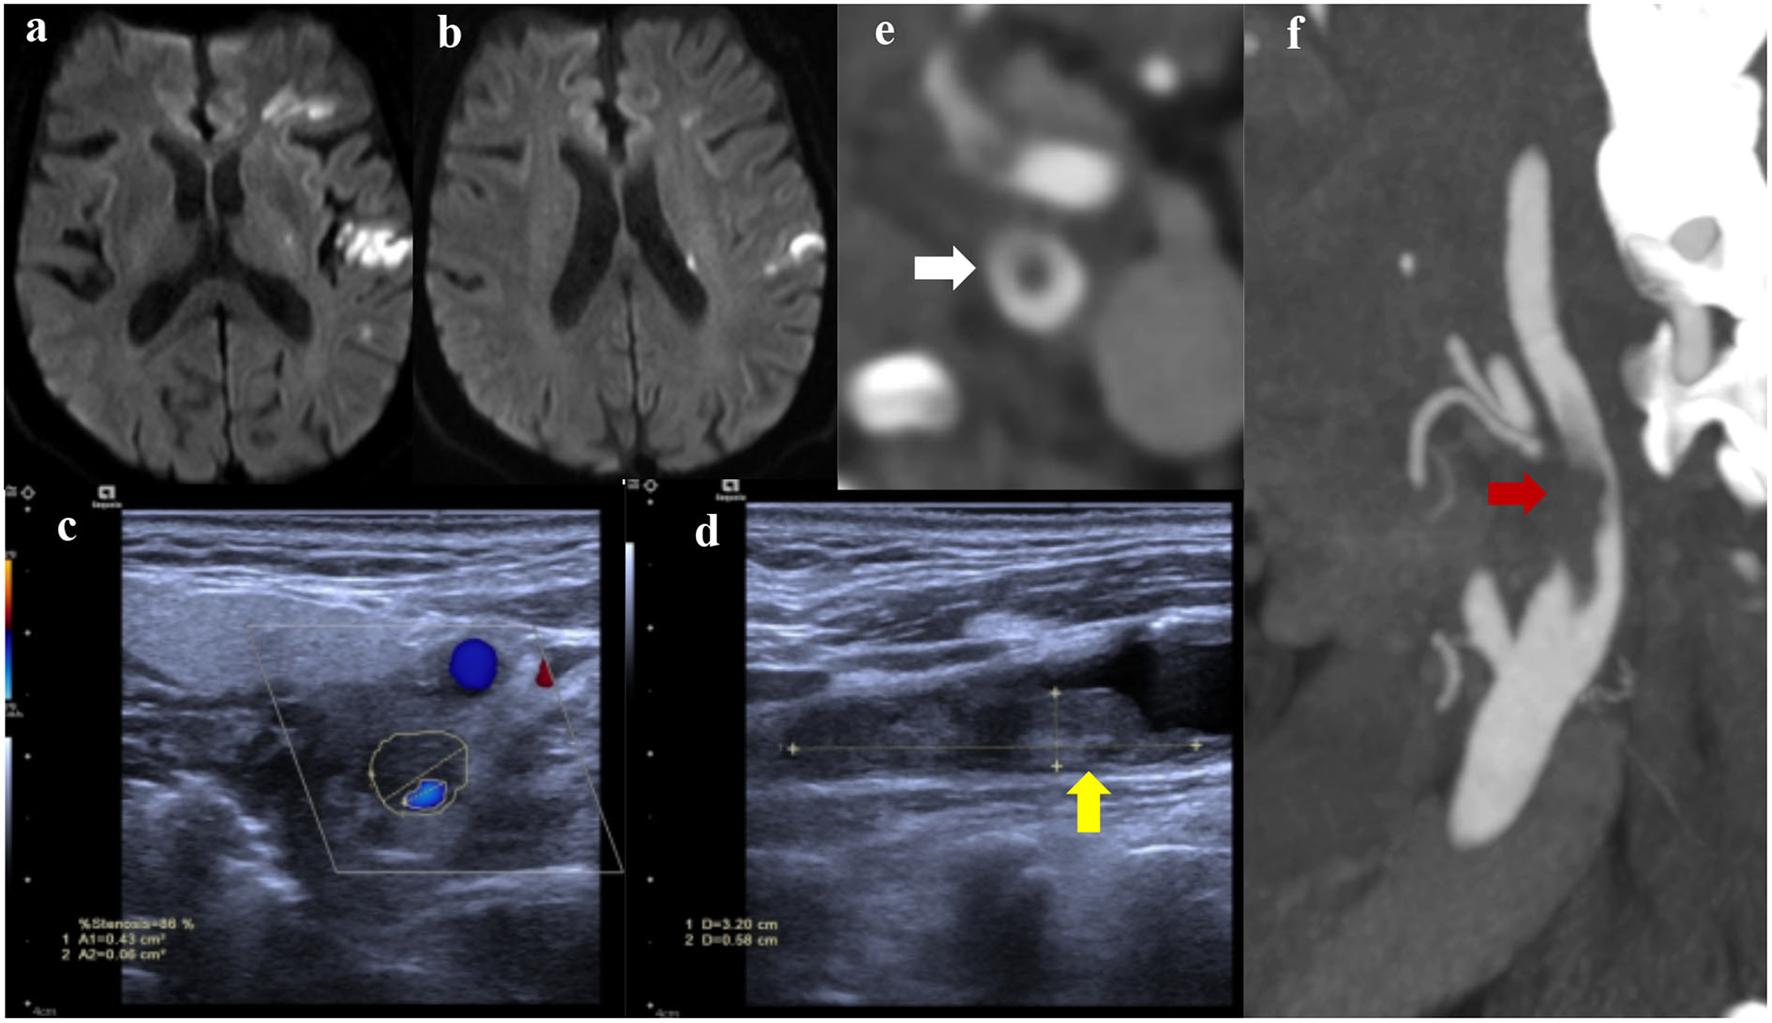

Figure 2

Diffusion-weighted imaging (DWI) showed multiple infarctions in the left hemisphere (a,b); Carotid ultrasound (c,d) indicated a culprit plaque with local floating thrombus (yellow arrow), resulting in obvious stenosis of the left internal carotid artery; carotid CTA (e,f) presented the floating thrombus (red arrow) with a typical cross-sectional “donut sign” (white arrow).